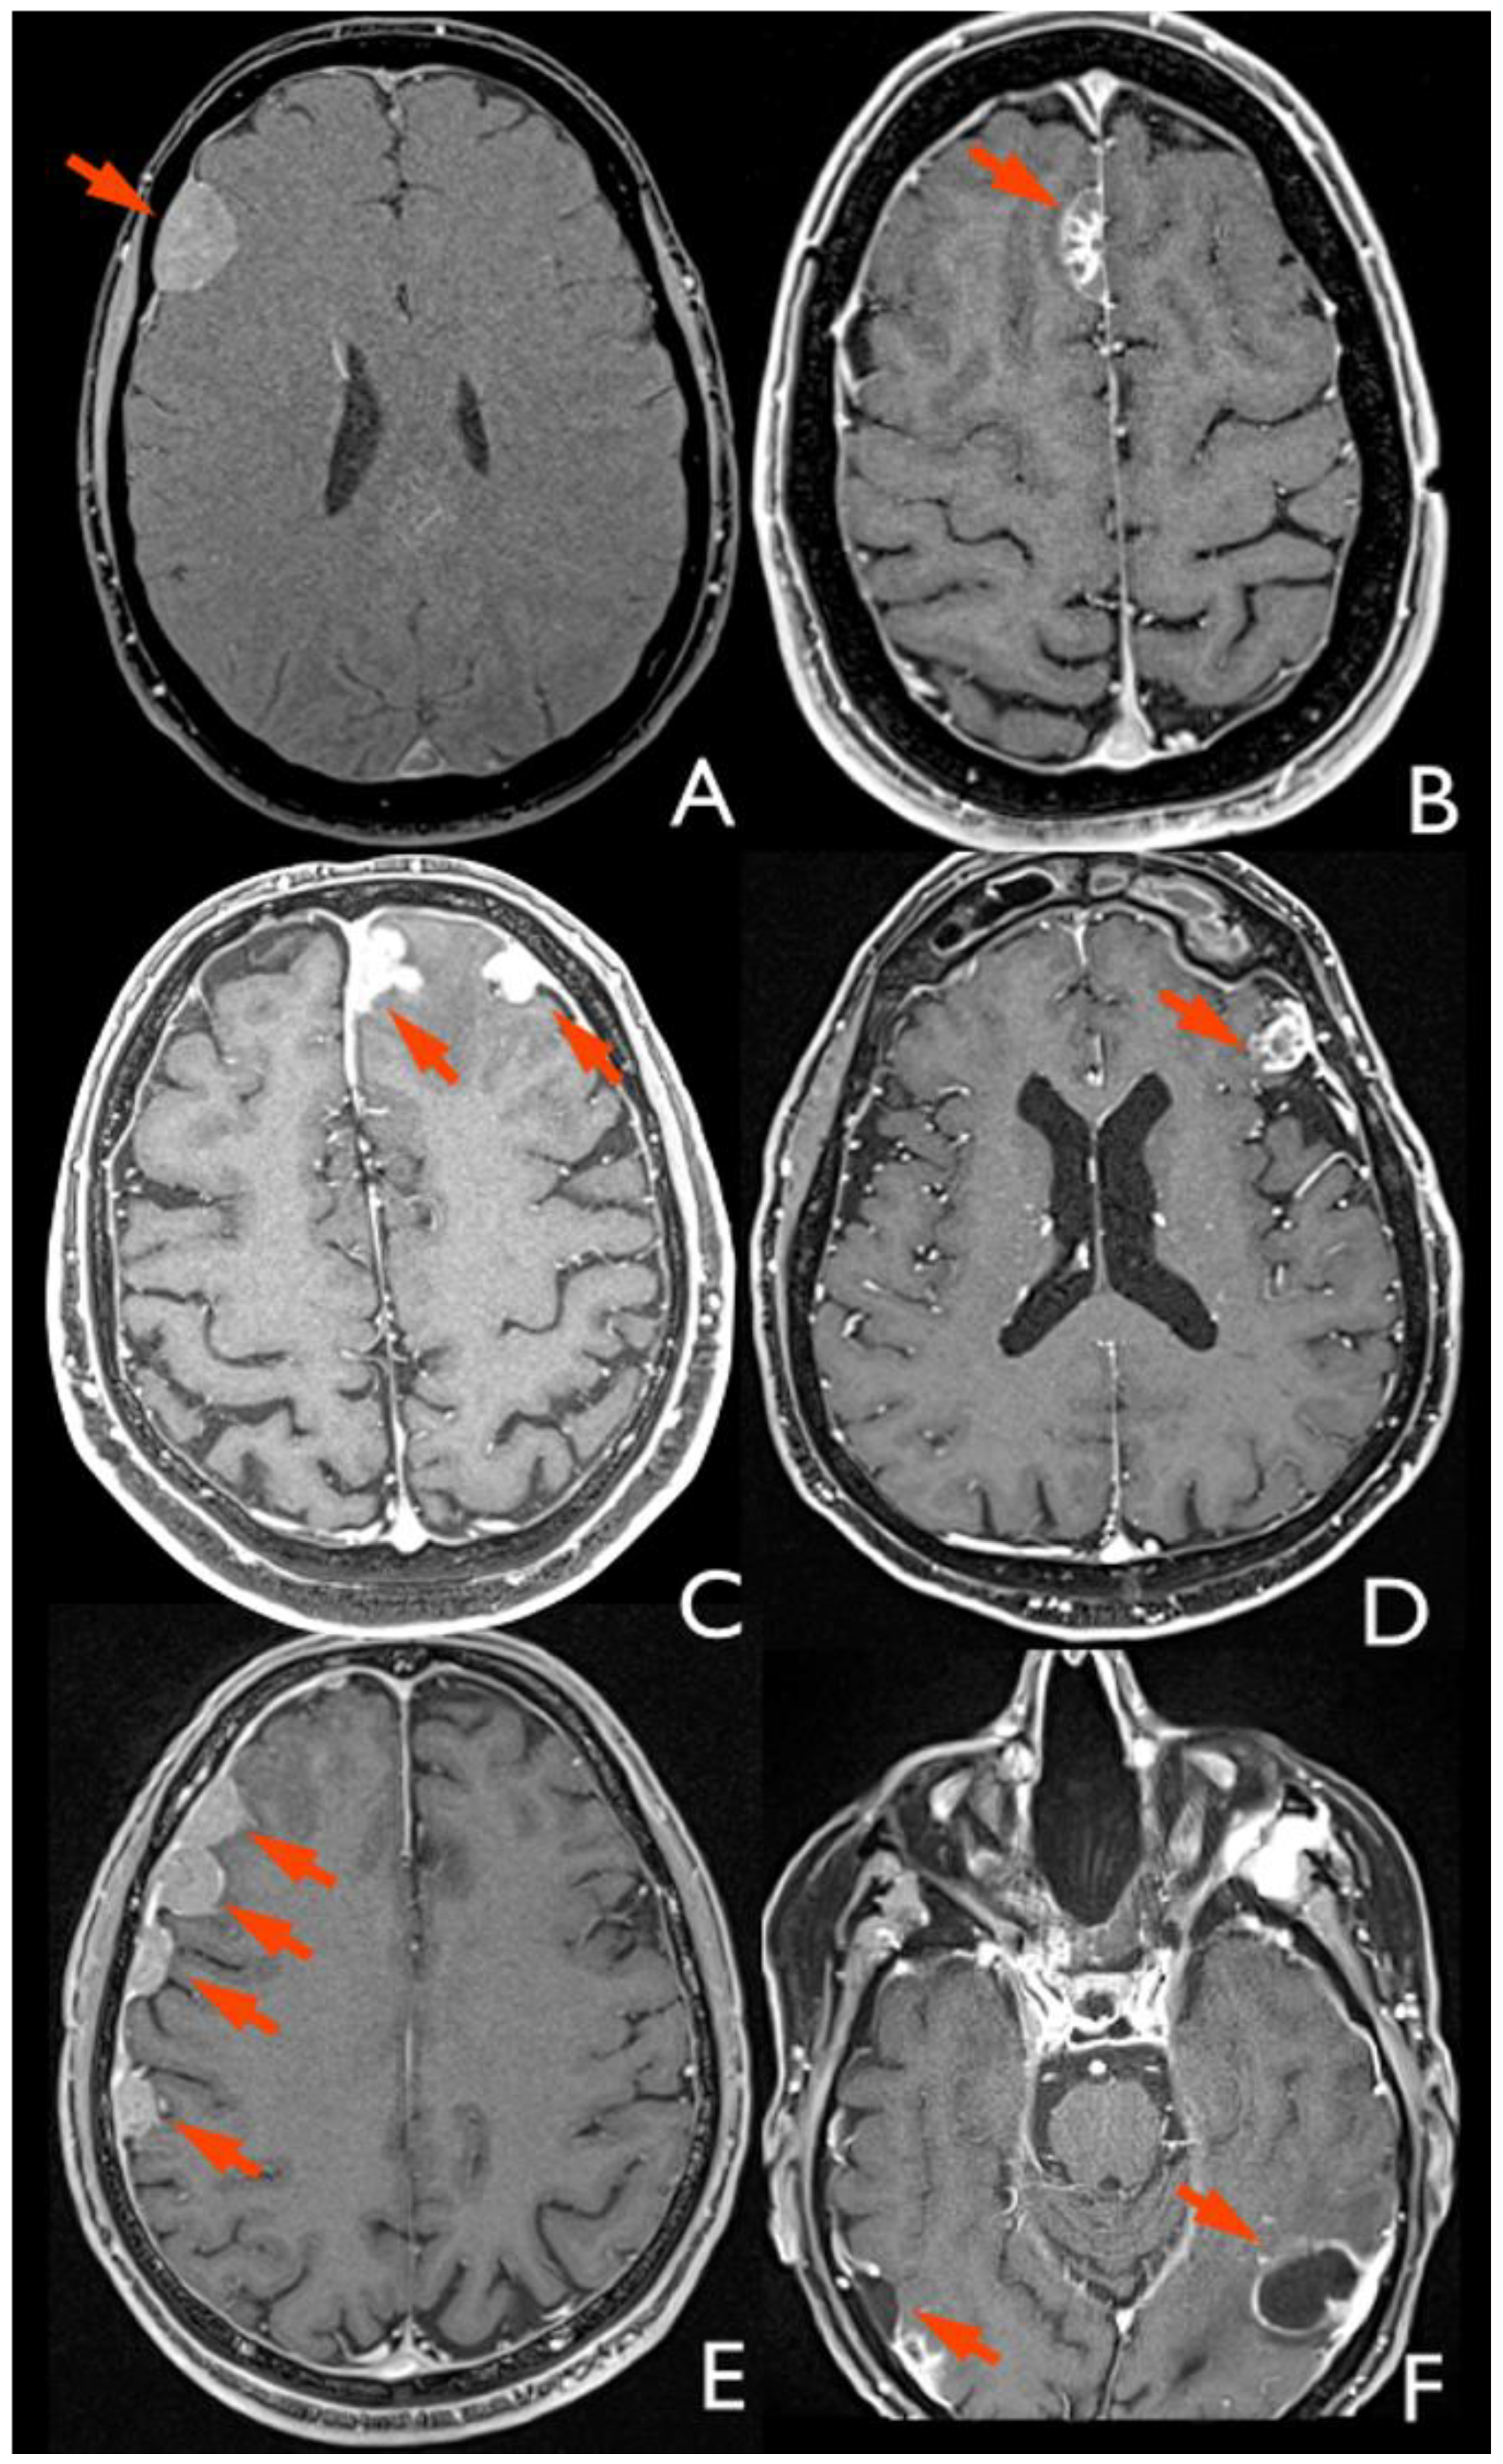

Preoperative and follow-up MRI studies of patients with MM were retrospectively analyzed by an expert radiologist (M.R.) to define signs of primary tumor transdural extension (i.e., brain edema and skull base/dural/parenchymal infiltration) and classify the recurrent lesions as either leptomeningeal or dural according to the following criteria (

Figure 1) [

2]:

Leptomeningeal metastases look like a diffuse coating overlying the parenchyma or multiple small nodules distributed along the cerebrospinal fluid (CSF) spaces.

Dural metastases show a characteristic “crescent” or biconvex shape, the second usually associated with brain displacement away from the inner table of the skull.

3.2. Radiological Analysis

The MRI of 15/17 (88.2%) patients with MM was evaluated. The remaining two patients were excluded because the available imaging was of inadequate quality for the purpose of this study.

All the metastases were dural; no leptomeningeal spread was identified. Fourteen (93.3%) patients showed one or more localizations to the dura of the cranial vault, while only one (6.7%) patient presented a single lesion located at the dura of the skull base, more than 1 cm away from the dural reconstruction. Among the 14 patients with cranial vault dural metastases, 4/15 (26.7%) had concomitant lesions at the dura of the skull base. The cranial vault lesions were prevalent in frontal, temporal, and parietal areas. Dural metastases of the skull base were in the anterior and middle cranial fossae. Finally, five (33.3%) patients presented a concomitant localization to the falx cerebri. No relation with the site (left or right) of the primitive tumor was observed. A total of 6 patients had bilateral MM (40%), 5/15 patients presented ipsilateral MM (33.3%), and 4/15 patients showed contralateral MM (26.7%). The topographic distribution of the MM is detailed in

Table 3.